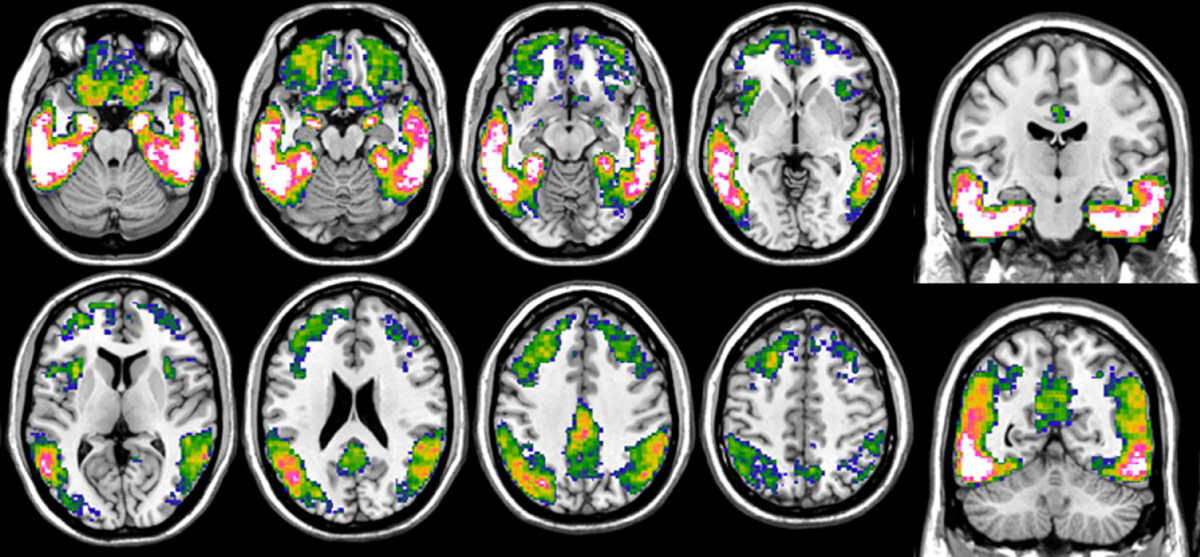

Alzheimer’s disease, one of the most common neurodegenerative diseases, leads to progressive loss of memory and autonomy. It is characterised by the accumulation of neurotoxic proteins in the brain, namely amyloid plaques and tau tangles. Due to the silent development of pathology over decades, very early diagnosis is of utmost importance to be able to take action as early as possible in the disease process.

La maladie d’Alzheimer, l’une des maladies neurodégénératives les plus fréquentes, entraîne une perte progressive de la mémoire et de l’autonomie. Elle est caractérisée par l’accumulation dans le cerveau de protéines neurotoxiques, la plaque amyloïde et la protéine tau. Évoluant à bas bruit pendant des décennies, son diagnostic très précoce est essentiel afin d’intervenir le plus tôt possible dans le processus pathologique.